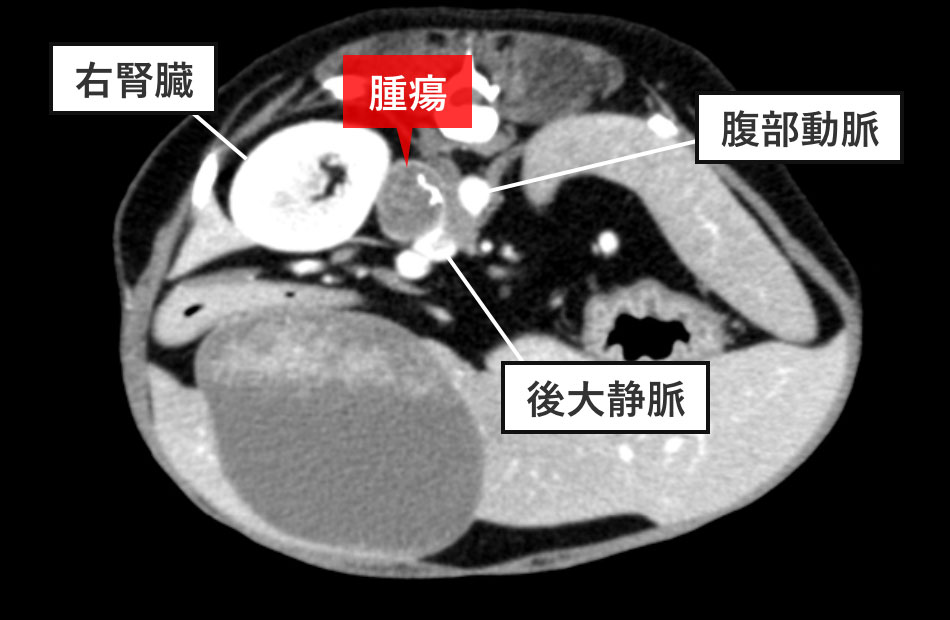

CT検査

右副腎は21mmに腫大し、一部石灰化を認めました。また、隣接する後大静脈内に腫瘍の一部が浸潤し腫瘍塞栓(腫瘍が血管内に詰まった状態)を認めました。下垂体に腫大はなく、他の臓器にも明かな転移を認めませんでした。

CT検査の結果から、腫瘍は右副腎だけではなく後大静脈内に広がっていることから、右副腎摘出術および後大静脈腫瘍栓の摘出を計画しました。